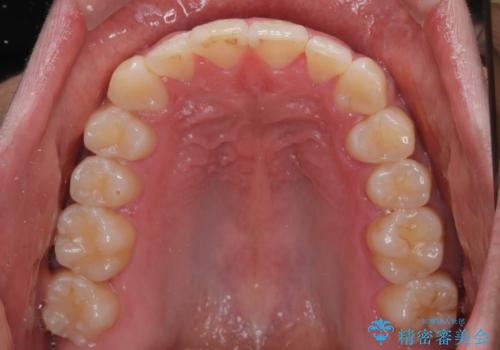

- 前歯のデコボコを治したいとのことで来院された患者様です。

上下顎ともに歯列全体の後方移動とIPR(歯と歯の間を削る)によってデコボコが解消するように設計し、インビザラインにより治療を行うこととしました。